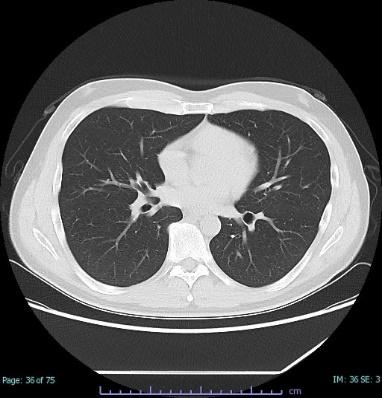

医療の分野では、放射線を使用した検査として、レントゲン検査・胃バリウム検査・CT検査・マンモグラフィ検査などがあります。